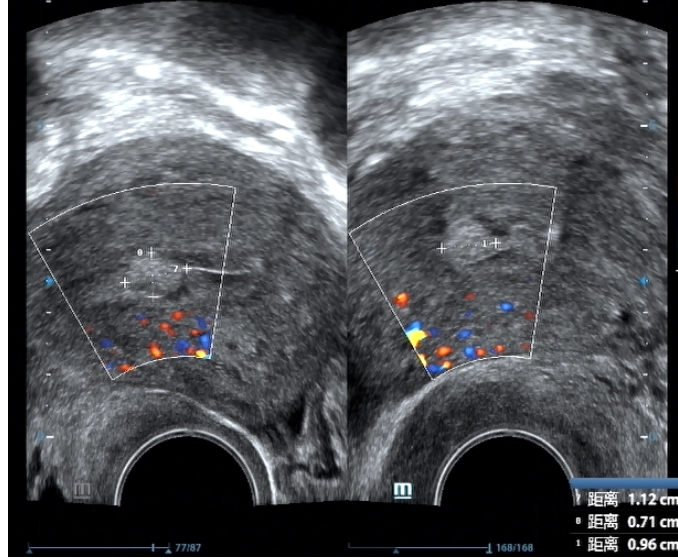

子宫内膜癌的超声表现

基本超声表现子宫内膜癌的B超特征以子宫内膜异常为核心子宫内膜厚度改变是重要指标,绝经后女性内膜厚度超过5mm需高度警惕,增厚范围可从数毫米至数厘米,且可能呈均匀或不均匀性内膜回声改变表现为不均匀,可见低回声等回声或高...